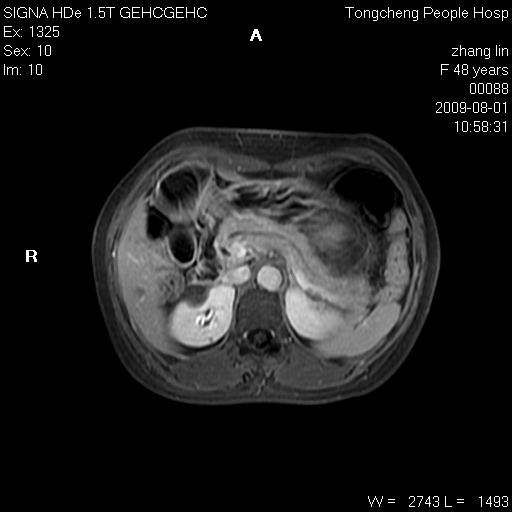

女,48岁。健康体检,彩超发现右肾占位性病变。平素健康。

临床诊断:右肾占位性病变,性质待定(囊肿?肿瘤?)。

上中腹部mr平扫+增强扫描,图像如下:

右肾上极见一类圆形病灶,t1wi呈等信号t2wi呈等高混杂信号,三期增强无强化,边界清---考虑囊肿出血。

同反相位均表现为等信号,病变无强化,考虑含蛋白的囊肿可能,弥散加权相或许有些帮助,